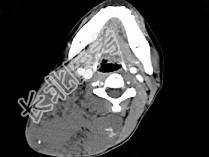

- 单项选择题女,32岁, 颈部包块8年余,包块逐渐长大, CT如图所示,最可能的诊断为 ( )

A、颈部神经纤维瘤

B、颈部横纹肌肉瘤

C、颈部巨大血管瘤

D、颈部神经鞘瘤

E、颈部异位甲状腺